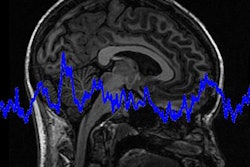

T2-weighted MRI scan of the head: transverse and sagittal views. Red arrows show high-intensity signal nodular lesion in the left upper eyelid. Image courtesy of BMJ Case Reports.An MRI scan of the orbit was performed, and it revealed a well-defined ovoid nodule measuring 8 x 4 x 6 mm. Features on the MRI scan were consistent with a cyst with proteinaceous content, Patel and colleagues reported. There were no other features of any foreign body.

They credited MRI with a radiofrequency surface coil as key to helping them detect the lens, thanks to the imaging modality's submillimeter resolution.

"This alternative method of imaging may have provided better visualization of the eyelid anatomy and possibly identified the foreign RGP lens in situ," they concluded.